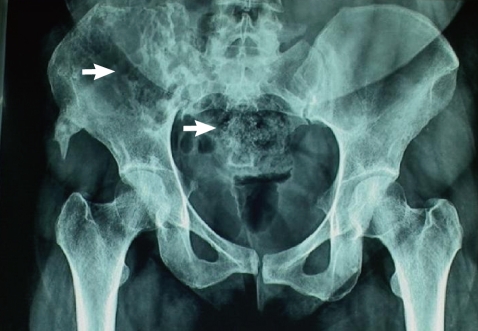

Fig. 1). She continued with pain and follow-up CT reviewed after 8 months revealed extension of the disease. The patient was then referred to our hospital. On physical examination, local tenderness was present on the back of the right limb and hip. The range of motion of the right hip was painful and restricted. No distal neurovascular deficits were present. Blood investigations were within normal range. Surgery was planned for removal of the residual disease. The preoperative MRI and CT showed progression of the disease. The CT showed a multiloculated cystic lesion (

Fig. 2) involving the medullary cavity of the right iliac bone resulting in irregular lytic destruction and extending across the right sacroiliac joint into the right half of the sacrum, right sacral foramina, and adjacent soft tissues. Resection of the hydatid cyst of sacroiliac region with allograft and autograft (rib graft) with lumbosacroiliac fixation was done.

Fig. 2CT revealed a multiloculated cystic SOL involving the medullary cavity of the right iliac bone and causing irregular lytic destruction extending into the right SI joint, right half of the sacrum, and right sacral foramina.